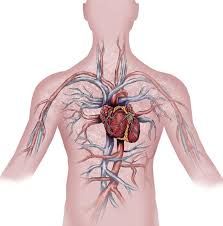

Le cœur fait partie de quel système ?

Qu’appelle t-on un système circulatoire ?

Quel est le rôle du système circulatoire ?

Le cœur fait partie du système circulatoire.

Un système circulatoire est un système d’organes en circuit (groupes) permettant le déplacement de liquide dans l’organisme.

Rôle du système circulatoire

Le système circulatoire a pour rôle le transport et l’échange interne des ressources (notamment nutritive et oxygène) vers les parties de l’organisme ainsi que de se charger de la collecte de déchets.